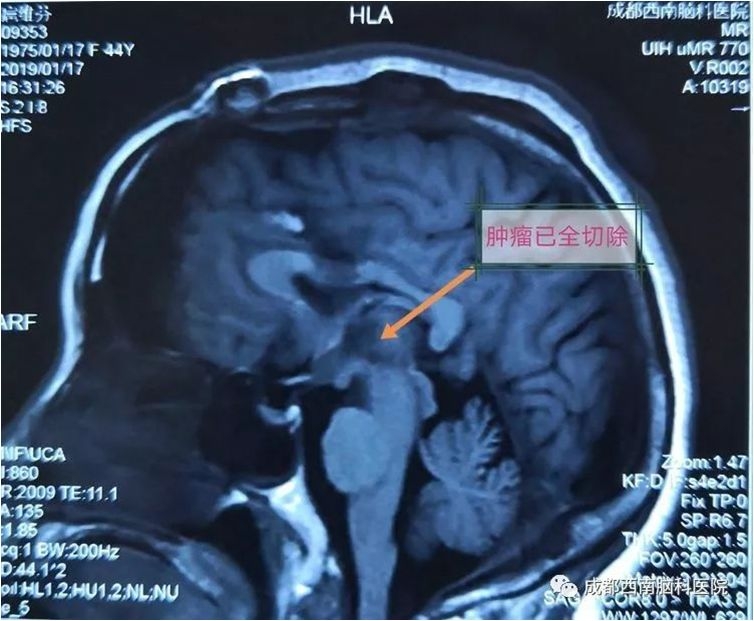

颅眶沟通性肿瘤切除手术

术前

术后(肿瘤全切)